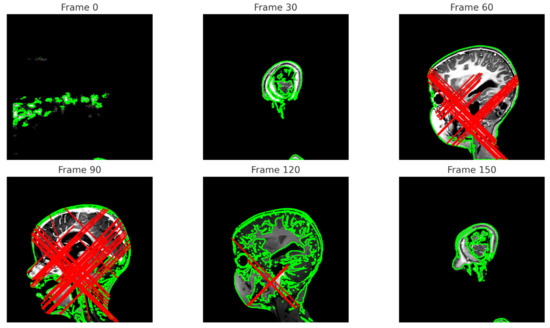

- Extent of Frame Extraction

- In the frontal plane, only the first 10 frames are extracted, potentially limiting the full video sequence analysis. In the sagittal plane, all 180 frames are extracted, allowing for a more comprehensive video sequence analysis;

- Marking Methodology

- In the frontal plane, potential tumor regions are marked with green contours. In the sagittal plane, potential tumor regions are marked with red rectangles;

- Detail of Analysis

- The frontal plane suggests further frame analysis without providing details on the needed clinical information, while the sagittal plane clearly suggests the need for additional clinical or radiological information for a more precise analysis.